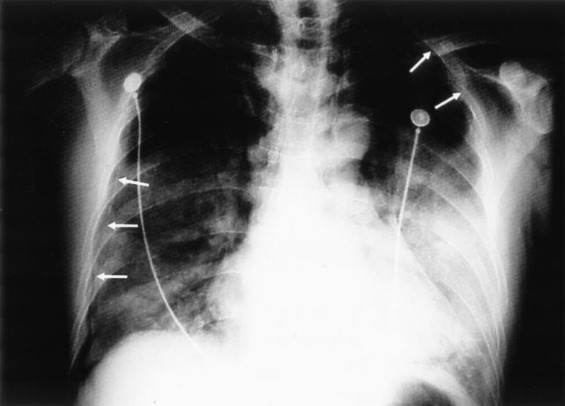

A 47-year-old man who was a nonsmoker with no significant medical history presented with a 2-day history of acute onset of fever, chills, and severe myalgia. He was a radiographer at PWH who had been in close contact with SARS patients for the 3 weeks since the initial outbreak. His chest radiograph showed diffuse bilateral pulmonary infiltrates at the time of hospital admission. Treatment with broad-spectrum antibiotics, ribavirin, methylprednisolone, and convalescent serum was given with initial clinical improvement. On the 32nd day after hospital admission, he was noted to have a sudden increase in dyspnea. Chest radiography confirmed a left pneumothorax with parts of the left lung adherent to the parietal pleura as a result of postinflammatory adhesions (Fig 1 ), creating several loculations of air and fluid within the left pleural space. The pneumothorax was managed with a chest tube. However, despite suction of 10 cm H2O from the chest drain, the chest radiograph showed that the left lung had only partially reexpanded, with several large loculations of air still remaining. A CT scan of the thorax confirmed the presence of loculated air pockets, which were not adequately drained, and showed diffuse, patchy inflammatory changes in both lungs, with a “honeycomb” appearance that was similar to that of mild bronchiectasis (Fig 2 ). A pigtail catheter was inserted into the largest loculation under ultrasound guidance. The pigtail catheter then was replaced with another chest tube for better drainage, and both drains were set to suction at 10 cm H2O. Symptomatic relief of the dyspnea was achieved, with improved lung reexpansion seen on chest radiography. An air leak persisted from both drains but eventually resolved with conservative management after 21 days, after which both the drains were successfully removed.

FIGURE 1.

Chest radiograph of the patient in case 1 on the occurrence of a left pneumothorax with loculations. Note the fluid levels in the left middle zone and the mild pneumomediastinum. There are patchy pulmonary infiltrates and consolidations, which are typical of SARS, apparent in both lungs.